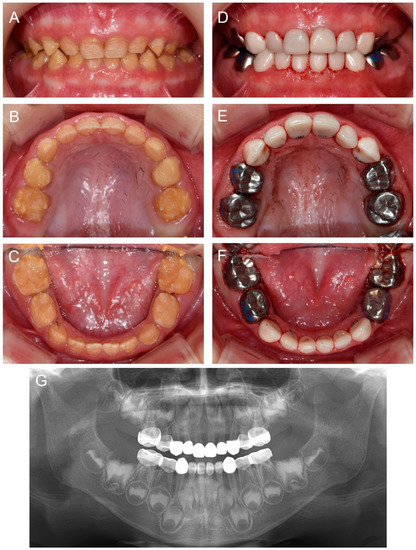

About 10 months after the first visit of the proband, a cousin of the proband presented for the management of the affected dentition at age 2Y. Oral hygiene instruction was given, and the same preventive measure was recommended. Completion of deciduous dentition was observed at the six-month follow-up, and discomfort in the mandibular posterior area was reported a month later. Full-mouth restoration was performed under outpatient GA at age 2Y11M. The deciduous mandibular anterior teeth were treated with celluloid resin crowns, because there was not enough interdental space for zirconia crowns (Figure 4).

Figure 4.

Clinical photos and panoramic radiograph of the affected individual (IV:1). (A–C) Clinical photos of the proband before the treatment at age 2 years 11 months. (D–F) Clinical photos of the proband after the treatment. The deciduous molars were treated with stainless steel crowns, and the deciduous canines and maxillary anterior teeth were treated with zirconia crowns. The deciduous mandibular anterior teeth were treated with celluloid resin crowns. (G) Panoramic radiograph at age 4 years 9 months.